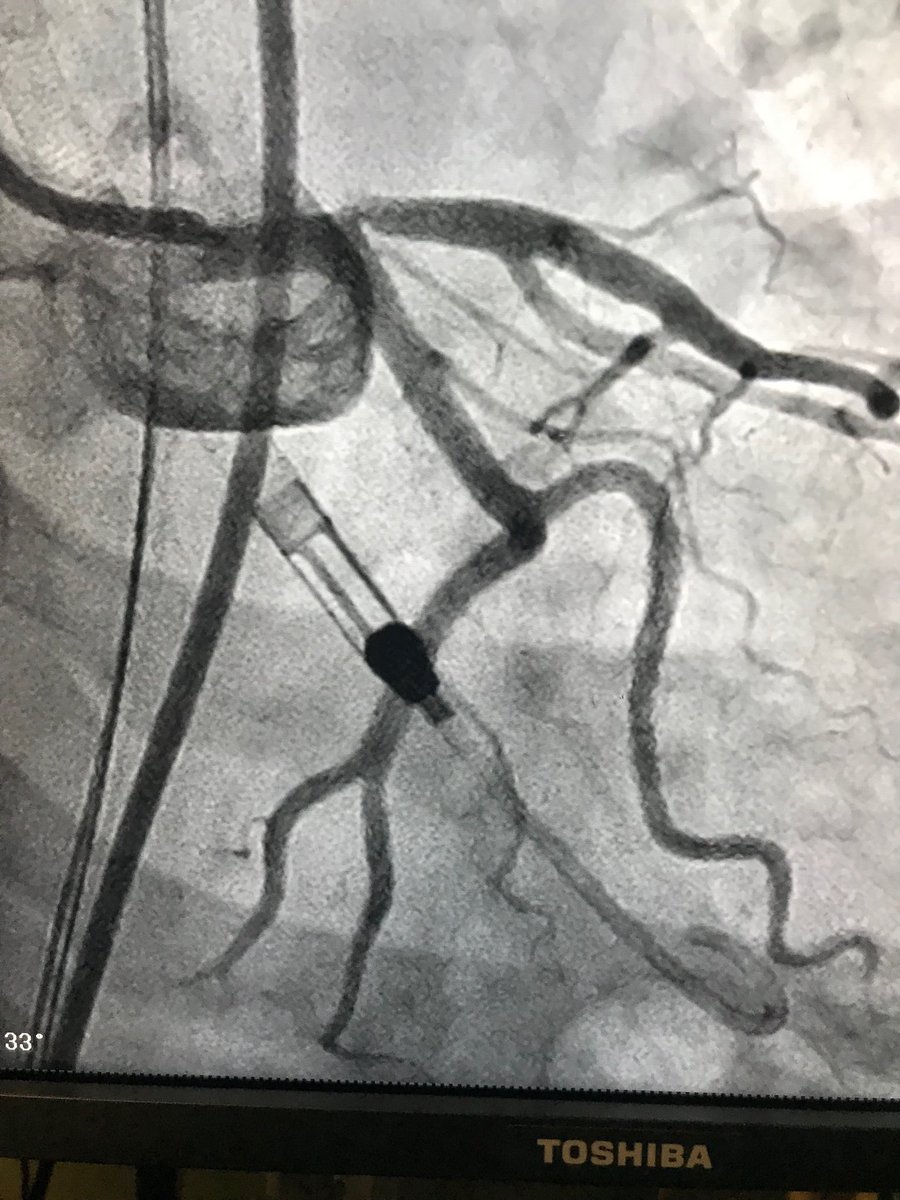

#pad #cardiotwitter#cto. 55 m dm, claudicant.no runoff.#pedalaccess , Antero and retro approach. #doubleballoon , #safari .#dcb.#supera .good dp pulse. Home same day.

istentem's tweet image. #pad #cardiotwitter#cto. 55 m dm, claudicant.no runoff.#pedalaccess , Antero and retro approach. #doubleballoon , #safari .#dcb.#supera .good dp pulse. Home same day.